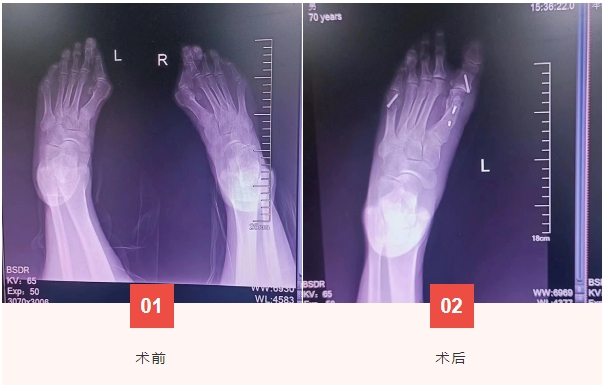

近日,骨一科接诊一位双足拇外翻患者。患者因为双足拇外翻20年,行走困难,疼痛加重6年多,严重影响日常生活,来院入住骨科一病区。入院后,科室经讨论决定给予手术治疗,顺利施行拇外翻截骨与功能重建术,患者及家属对术后效果很满意。

拇外翻只是不好看而已,不疼就不需要治疗?不!拇外翻需尽早治疗,否则易引发腿部肌肉疲劳,髋骨重心前移,脊椎变形,等到畸形特别严重时,矫正起来非常困难。超微创无痕术治疗拇外翻具有复发率低,手术方法简便、高效、切口小、恢复快、并发症少、安全的特点。